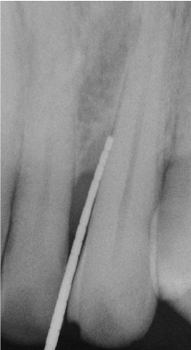

Fotos dos casos clínicos